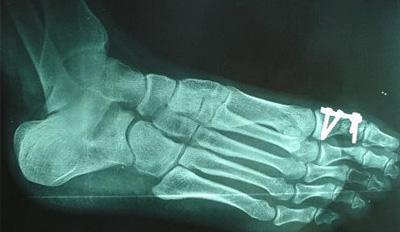

趾骨骨折一般指跖骨骨折,跖骨骨折多因重物打擊足背、輾壓及足內(nèi)翻扭傷引起。跖骨干骨折因相鄰跖骨的支持,一般移位不大。第2、3跖骨頸部易發(fā)生應(yīng)力骨折(疲勞骨折)。第5跖骨基部骨折是由于足突然內(nèi)翻,腓骨短肌猛烈收縮撕脫造成,很少移位,需與該部未閉合的骨骺相鑒別。